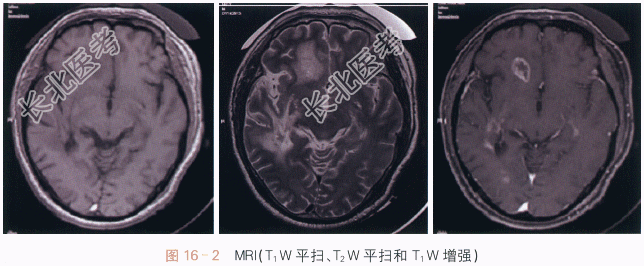

影像学资料如图16-1、图16-2所示。

读片分析:颅脑CT平扫显示右侧额叶及右颞枕叶片状低密度影,其内密度不均。周围脑组织呈水肿性低密度,邻近脑沟、裂变窄变浅。

颅脑平扫加强化MRI检查显示:右侧额叶及右颞枕叶见一长T₁等长T₂异常信号,注入对比剂后呈明显不均质强化,中间呈坏死性不强化改变。病变强化后边界不清,病变定位脑内,非硬脑膜起源,未见脑膜尾征。周围脑组织可见血管源性水肿征象,累及皮质下和深部白质。MRI检查显示较CT扫描清晰、明显。结合患者临床表现,考虑患者为转移瘤。